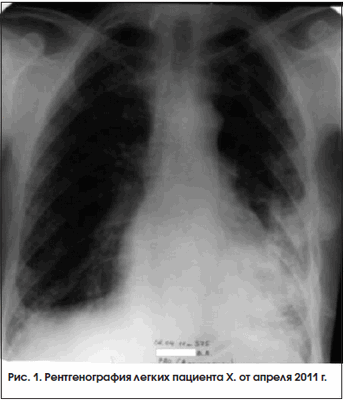

В конце января 2011 г. состояние пациента ухудшилось, прогрессировали мышечные боли и слабость в мышцах, озноб, появился субфебрилитет, сохранялись кашель и одышка, в биохимическом анализе крови было выявлено повышение КФК до 786 ммоль/л, ЛДГ – до 864 ммоль/л. На ЭКГ в начале февраля 2011 г. была отмечена отрицательная динамика, не исключавшая острую коронарную патологию, которая в дальнейшем не была подтверждена. На ЭКГ в этот период были выявлены признаки легочной гипертензии. Внутрисуставное введение ГКС было прекращено, дозы НПВП снижены. В начале марта 2011 г. при повторной рентгенографии тень, подозрительная на инфильтрацию, сохранялась без изменений, и пациент был направлен в туберкулезный стационар. В период с 15.03 по 22.04.2011 г. пациент находится в ПТКБ № 3 им. Захарьина с диагнозом «диссеминация неясного генеза» (рис. 1), там же была проведена операция – открытая биопсия левого легкого. При исследовании полученного материала выявлена неспецифическая пневмония с интраальвеолярным фиброзом. Схема лечения и рекомендации консультированы проф. И.П. Соловьевой. Пациент выписан с диагнозом «интерстициальная пневмония с интраальвеолярным фиброзом».

В период после назначения метотрексата и преднизолона до настоящего времени отмечается устойчивая положительная динамика состояния пациента. Он ведет активный образ жизни, исчезли кашель и одышка, нет ознобов и субфебрилитета, значительно уменьшились боли и отек в суставах, расширился объем движений. Несмотря на формирование контрактур в суставах кистей и лучезапястных суставах (рис. 2 и 3), обслуживает себя и выполняет работу по дому. При рентгенографии кистей в апреле 2012 г. суставные поверхности прослеживались, их контур четкий, кистообразной перестройки костной ткани нет. При рентгенографии легких от 15 апреля 2012 г. определялись двусторонний фиброз в нижних отделах легких с обеих сторон, формирование «сотового» легкого (рис. 4). В настоящее время получает метотрексат 10 мг/нед., преднизолон 10,125 мг/сут. Биохимические показатели снизились и составляют: КФК – 426 ммоль/л, КФК-МВ – 64 Ед/л, ЛДГ – 603 ммоль/л, СОЭ – 14 мм/ч.